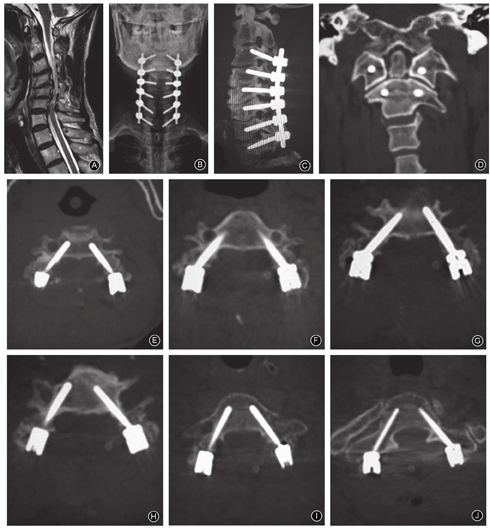

椎弓根螺钉位置:0级486枚、Ⅰ级8枚、Ⅱ级3枚、Ⅲ级0枚(表1,图3,图4,图5);寰椎置钉准确率为98.6%,枢椎准确率为97.7%,下颈椎准确率为97.6%。11枚螺钉穿破椎弓根皮质(Ⅰ级+Ⅱ级,表2),其中3枚螺钉为误置,但均为Ⅱ级(突破皮质<1.75 mm),穿破椎弓根内侧壁2枚(分别为C1和C4),穿破外侧壁1枚(C2),无穿破椎弓根上壁及下壁者。置钉的准确率为97.79%(0级),螺钉的偏出率为2.22%(Ⅰ级+Ⅱ级+Ⅲ级),椎弓根螺钉总误置率为0.60%(Ⅱ级+Ⅲ级)。

105例患者均顺利完成手术,术中置入510枚螺钉。由于6例患者(13枚螺钉)无术后CT无法进行测量,最终99例患者记入统计,共置入497枚螺钉(上颈椎201枚、下颈椎296枚)。椎弓根螺钉位置:0级486枚、Ⅰ级8枚、Ⅱ级3枚,Ⅲ级0枚。11枚螺钉穿破椎弓根侧壁(Ⅰ级+Ⅱ级),其中3枚螺钉为误置(均为Ⅱ级),穿破椎弓根内侧壁2枚,穿破外侧壁1枚,无穿破椎弓根上壁及下壁者。置钉的准确率为97.79%(0级),总误置率为0.60%(Ⅱ级+Ⅲ级,3/497)。所有患者术后随访12~30个月,平均(20.6±5.2)个月。植骨愈合情况良好,术中及术后均未出现脊髓、神经根、血管损伤等并发症。随访期间亦未见螺钉松动、断裂现象。创伤患者随访期间症状较术前有明显好转;非创伤患者术后6个月JOA评分较术前有明显提高。

本组105例患者(510枚螺钉)均顺利完成手术,由于6例患者(13枚螺钉)无术后CT资料,无法测量,最终计入统计为99例患者(497枚螺钉,上颈椎201枚、下颈椎296枚)。

本研究中置钉的准确率为97.79%(0级),且所有随访患者术中及术后均未出现脊髓、神经根及血管损伤等;随访期间亦未见内固定物松动、断裂现象,且骨愈合良好,表明该置钉方法比较精准。不过术后CT三维重建仍提示有11枚螺钉穿破椎弓根骨皮质,但其中误置仅为3枚(Ⅱ级);在节段分布上,11枚螺钉中穿破C3、C4节段椎弓根5枚(45.5%)。国内外研究表明,C3、C4椎弓根宽度较小(尤以亚洲人明显),横向角较大,此外若术中显露不充分,加上两侧肌肉及切口的阻挡,使得C3、C4节段置钉难度明显增大,增加螺钉穿破椎弓根骨皮质的风险;在穿破方向分布上,11枚中突破椎弓根内侧壁4枚(36.3%),外侧壁5枚(45.5%),上壁及下壁各1枚(占9.1%)[10,12,13,23,24]。